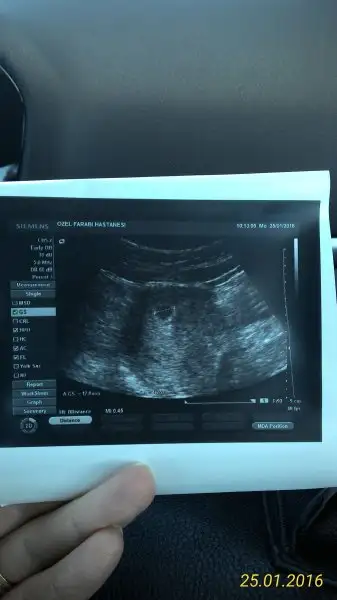

ben bu sayfadan bakıp o aydınlık kısmın plasenta olduğunu sanmıştım, yanılmışım demek ki, sağlıklı sıhhatli olsunlar da kız erkek fark etmez, 5+2 deki var arada başka yok canım, o da karından onu göndereyim anlaşılır olursa

• P_20160125_103816_1_p.webp

P_20160125_103816_1_p.webp

11,4 KB · Görüntüleme: 459

Cnn bu resmine göre kız bebek ama yolkun tam konumunu görmem için bir önceki ultrason a bakmam gerekiyor. Bu ultrasonda yolk kesesinin konumuna göre erkek olma ihtimali de var

Ramziye göre kıza işaret ediyor... sen ilk kalp atimini gordugunde doktor kan akimini da gostermedi mi hani o kirmizili mavili doppler gibi... ışte o kan akımının olduğu yer plesanta oluyor.